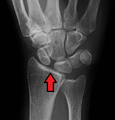

Scapholunate ligament disruption associated with a colles fracture